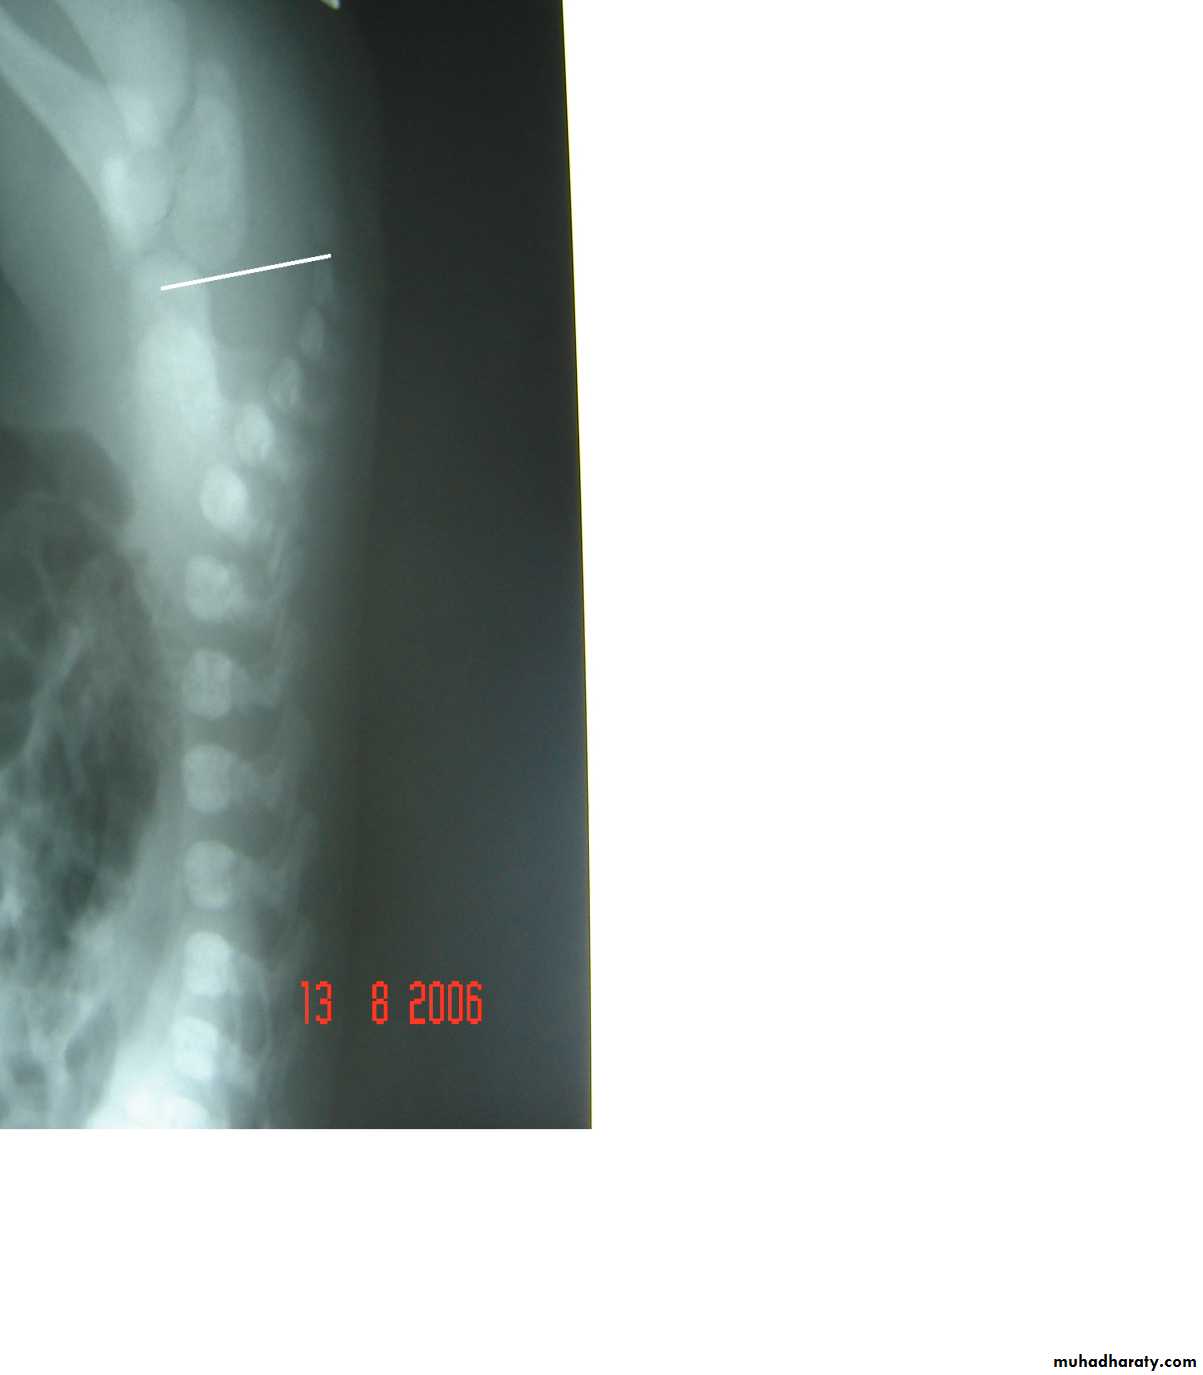

Subcostal incision